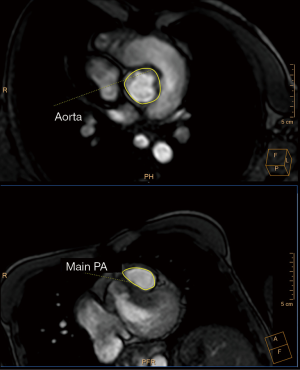

Tetralogy of Fallot (TOF) is the most common cyanotic congenital heart disease (CHD); its prevalence is estimated at around 5/10,000 births (1). Furthermore, due to the success of pediatric cardiac surgery and pediatric cardiology, the population of adults with TOF is growing steadily, with over 90% of children with CHD now surviving into adulthood (2). This relatively new population of adult patients, which now outnumbers the pediatric TOF population, poses further challenges for clinicians. Cardiac imaging has rapidly evolved, from relying exclusively on cardiac catheterization and chest radiography (Figure 1) to today’s more advanced imaging techniques: echocardiography, cardiac magnetic resonance (CMR), and cardiovascular computer tomography (CT) (3). Because of the complex nature and diversity of these population, as well as the limitations of each modality, it is increasingly recognized that an expert multidisciplinary team with a multimodality imaging approach is necessary for their clinical management (4).

In clinical practice, CMR’s principal advantage over TTE is the accurate quantification of biventricular size and function, and it is the gold standard for volume and flow assessment in TOF (12) (Figure 3). Optimal timing for PV replacement in PR is challenging, and current recommendations rely on RV volumes, which are performed with cine steady-state free precession (SSFP) sequences. Generally, PV replacement should be indicated before reaching an RV end-diastolic indexed volume of 160 mL/m2 or an RV end-systolic indexed volume of 80 mL/m2 (10,22). These are CMR thresholds considered a point of no return beyond which RV function and reverse remodeling recovery would be expected to be limited after PV replacement (23,24). On the other hand, intervening too early potentially exposes patients to reinterventions later in life. Consequently, since the indication for PV replacement depends on CMR, it should be indicated in all patients prior to deciding intervention. Cine sequences also allows us to assess RVOT wall motion and geometry, including obstruction to flow, detect valvular regurgitation and stenosis (Figure 4) and residual shunts, and evaluate aortic dilatation.